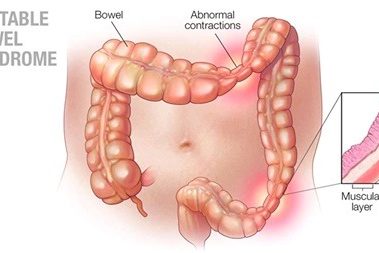

Ο πρωκτός είναι το τέλος του παχέος εντέρου, μέσω του οποίου τα κόπρανα αποβάλλονται από το σώμα. Ο πρωκτός διαμορφώνεται εν μέρει από τα εξωτερικά στρώματα του δέρματος και εν μέρει από το έντερο. Δύο μύες σε σχήμα δαχτυλιδιού, που ονομάζονται σφιγκτήρες μύες, ανοίγουν και κλείνουν το πρωκτικό στόμιο για να γίνει η κένωση του εντέρου. Το πρωκτικό κανάλι, το τμήμα του πρωκτού μεταξύ του ορθού και του πρωκτικού στομίου, έχει μήκος περίπου 4cm.